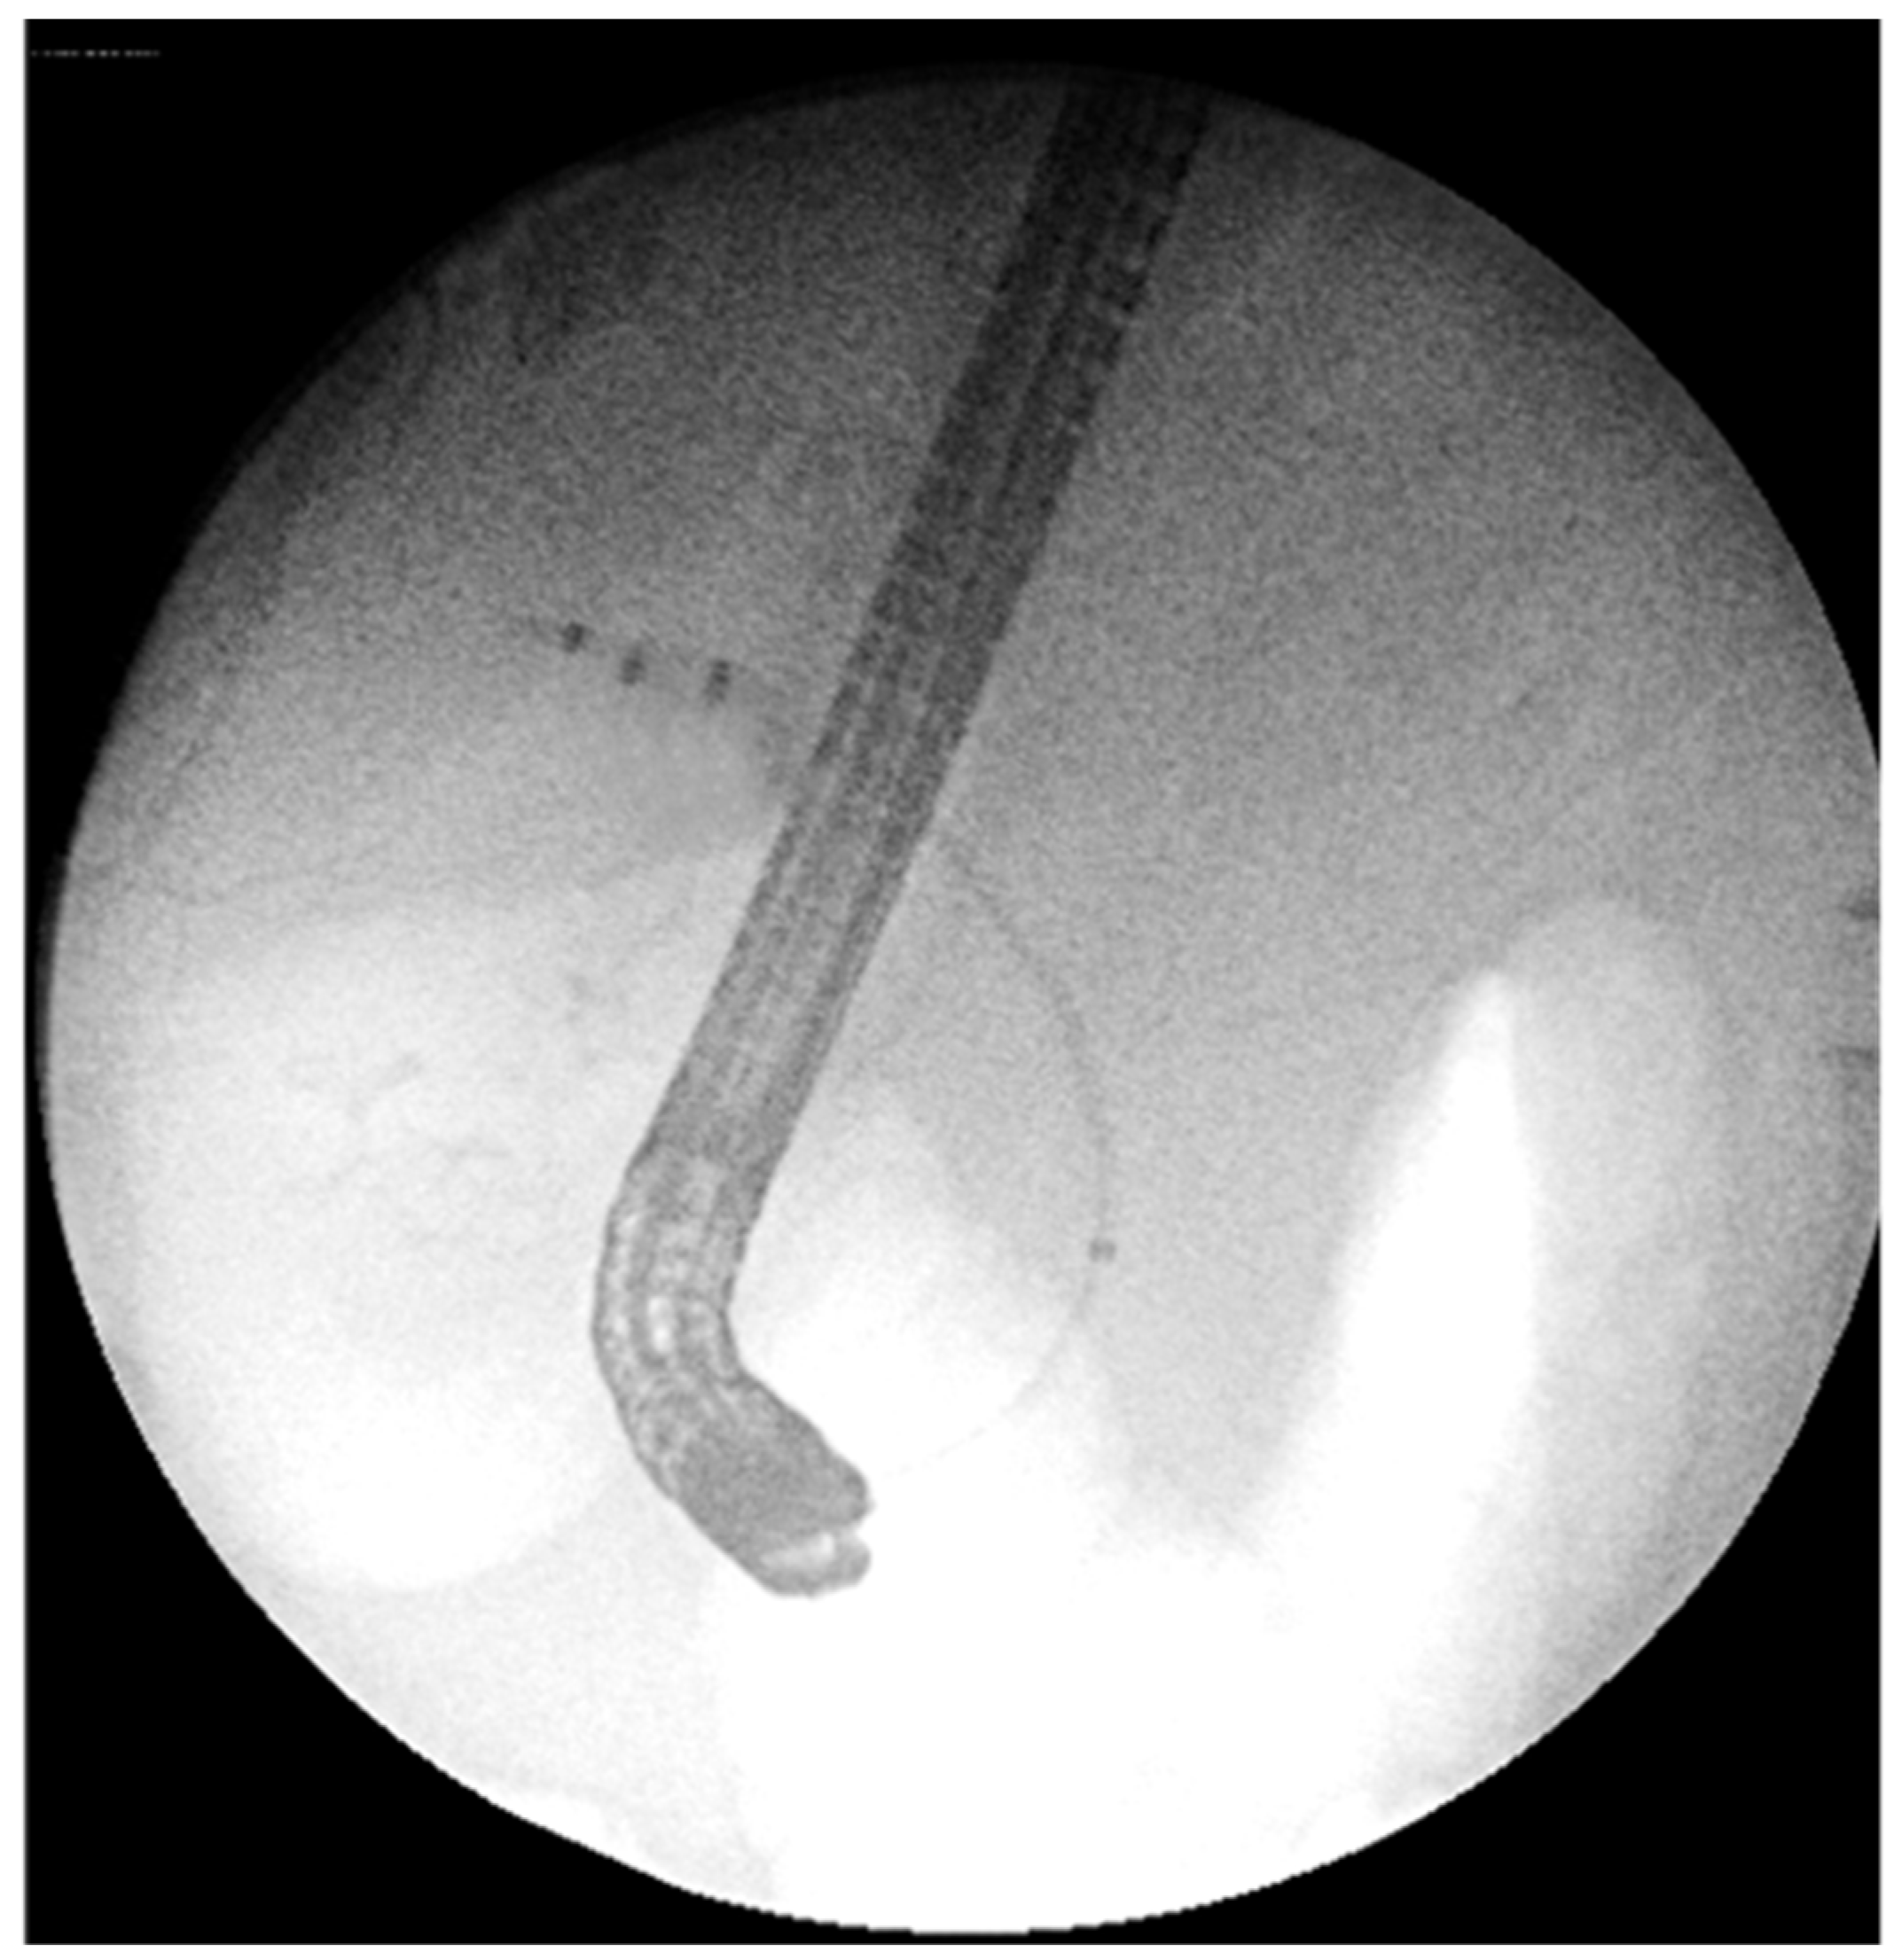

- 14.02: First ERCP showed normal bile ducts and papilla, no strictures or filling defects (Figure 2A).